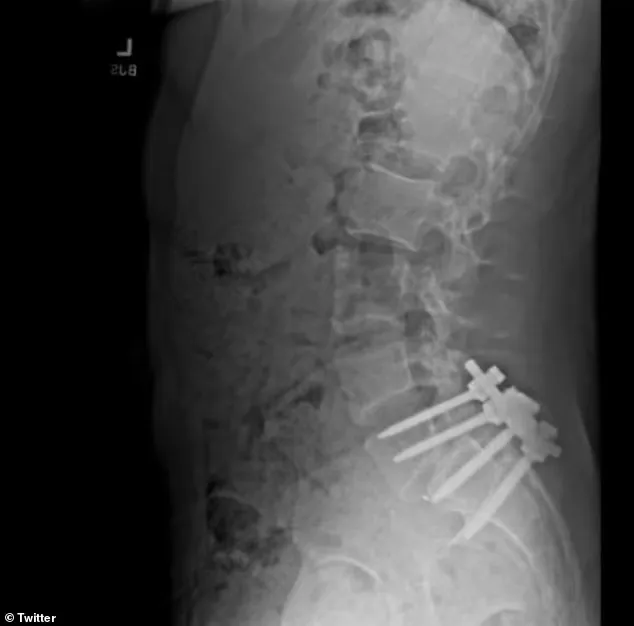

馬丁解釋説,曼吉奧內因一次衝浪事故而導致脊椎滑脱的背部狀況惡化,“他的脊椎有點錯位。他説他的下椎骨幾乎脱落了半英寸,我認為這擠壓了神經。”一次衝浪課後,曼吉奧內“在牀上躺了一個星期”:“這真的很痛苦,也很困難,你知道,當你二十出頭的時候,你不能做一些基本的衝浪運動。”

目前一個被認為是曼吉奧內的Reddit發帖者,談到了他小就患有一種叫做脊椎滑脱的背部疾病。脊椎滑脱是指脊柱中的一塊骨頭(稱為椎骨)滑出。這種情況通常會影響下背部,並且會非常疼痛。

同一位 Reddit 用户還發布了有關萊姆病和嚴重腦霧的投訴。該用户表示,他在兄弟會的“地獄周”期間開始遇到這些問題,並且他的成績隨後下滑。這位用户後來表示,一次衝浪事故導致他的背部和臀部“被鎖住”:“間歇性的麻木已經變成了持續的,我很害怕這會帶來什麼影響。”

《紐約時報》報道稱, 曼吉奧尼在2023 年接受了大手術,並在隨後的幾個月裏與朋友和家人失去了聯繫。